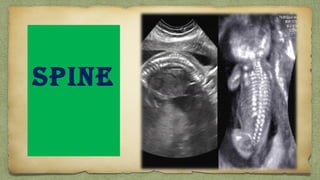

SPINE

๏ฑ Coronal or Sagital of entire spine:

๏ƒผ cervical

๏ƒผ Thoracic

๏ƒผ Lumbar

๏ƒผ Sacral

๏ฑ Transverse assessment of entire spine: Triangular 3

dots form closed triangle